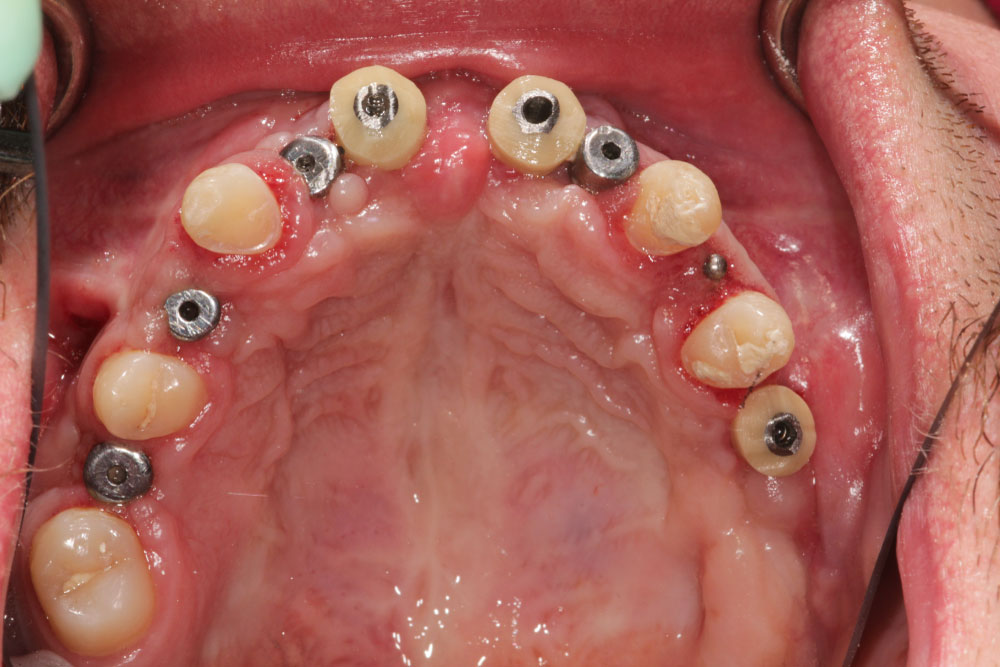

In preparation for the planned implantations, gaps were needed in the maxilla as well as in the mandible. For this, we lateralized, medialized and distalized the corresponding teeth, so called orthodontic volume optimizing [47], (Figure 7a and Figure 7b). In the meantime, the cones of teeth 31/41 and 11/21 could be extracted during the time of 12 months. The plates for osteosynthesis could be removed and the alveolar ridge of maxilla and mandible was augmented with the iliac bone graft in regio 11-13, 23/24, 31/41, and 35 (Figure 8 and Figure 9). After that, we inserted implants in the maxilla in regio 16, 14, 12, 22, 11, 21, 24, and 26 and in the mandible in regio 36, 34, 31/41, 44, 46 (SI Cace, SIConepiece for teeth 14 + 34). Concerning the teeth 31/41, a bone split was set (Figure 10). The other teeth were pre-grinded as preparation for the later prosthetics of crowns and bridges. A model was prepared in the laboratory.

After 6 months of healing, the implants could be revealed and individual gingiva formers were incorporated to shape the soft tissue (Figure 11).After additional three months, the final prosthetic device of high esthetic standard could be incorporated: Circonia for the maxilla and SiO2 ceramics for the mandible (Figure 12, Figure 13, Figure 14 and Figure 15).

Figure 11: Clinical situation after selected tooth extraction and implantation in region 16, 14, 12, 22, 11, 21, 24, 26. View Figure 11